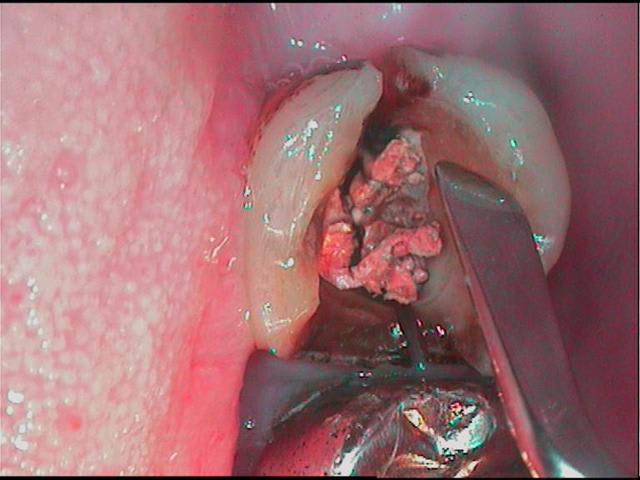

Je relance ce post pour avoir votre avis sur ce cas : jeune femme 25 ans en urgence douleur sourde d'apparition brutale sur 16 dévitalisée .Test morsure positif et papille mesiale enflammée , je démonte l'obturatio et voila ce que je mets en évidence ( il y a en plus un mv2 non obturé).Extraire d'emblée cette dent me fait mal au coeur : y aurait il un traitement à tenter ou que vous auriez réalisé avec succes ? ( la felure ne traverse pas entièrement la dent: localisée en mésiale )

Merci.